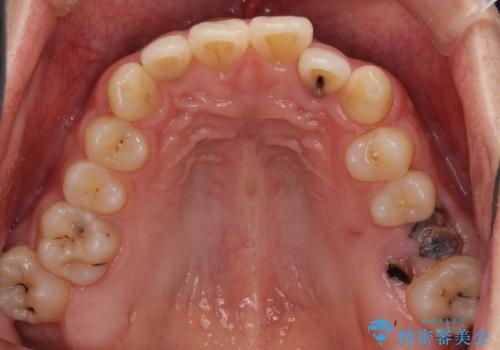

前歯のクロスバイトと抜歯が必要な奥歯の虫歯 インビザラインとインプラント治療

- 前歯のクロスバイトと、大学生のころから放置している虫歯を気にして来院された患者様です。

マウスピースでの矯正治療を希望されていましたが、前歯のクロスバイトは不十分な仕上がりや歯髄壊死などのリスクが高くなるため、術前にワイヤーで大まかに整えてからインビザラインにて矯正治療を行うこととしました。

奥歯の虫歯は抜歯が必要であったので、矯正治療前に抜歯をし、矯正治療と並行してインプラントによる補綴治療を行うこととしました。